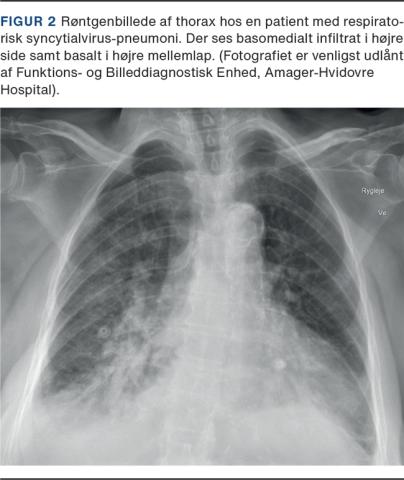

De senest introducerede CoV: SARS-CoV-1 fra 2003, MERS fra 2012 og SARS-CoV-2 har en høj aldersafhængig dødelighed. Alle tre menes at være zoonoser, som via mutation og menneskekontakt er blevet humant patogene. For SARS-CoV-1 er den samlede dødelighed omkring 15% [8] og for MERS omkring 34% [9]. For den ubehandlede SARS-CoV-2 er hospitalsdødeligheden 15-25% mens den samlede dødelighed i Danmark er < 1%, når der er justeret for alder og køn [10]. Typisk røntgenbillede af thorax af SARS-CoV-2 pneumoni med interstitielle infiltrater ses på Figur 1.

Billede